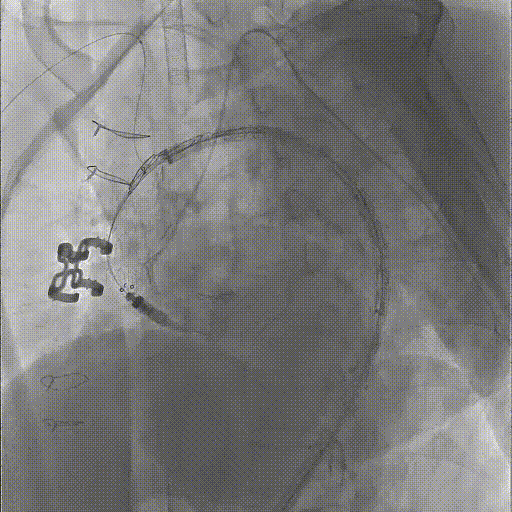

★ Case 3

男性,61岁,Bentall术后1年,主动脉弓部夹层;

既往史:高血压3级;

夹层动脉瘤CTA:A型主动脉夹层术后残余主动脉弓部夹层,头臂干及左颈总动脉根部夹层累及,向下累及胸腹主动脉至髂血管平面。

造影后经股动脉导入并释放限制支架

经股动脉导入主体支架,抓捕无名动脉预留导丝,支架导入升主动脉

造影定位后释放主体支架

经股动脉依次超选导入分支支架,释放并球囊扩张,术毕造影

三个穿刺点(双侧肱及单侧股动脉)无需颈部切口/穿刺